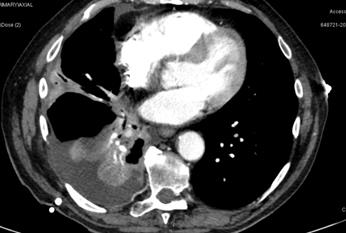

The patient was referred to the

cardio-thoracic surgeon and had a pleurocentesis

performed. After the drainage, the newer CXR demonstrated improvement in the

pleural effusion and unmasked a mass in the right lung which was previously

hidden by the fluid. There was right basal atelectasis and a small residual

right pleural effusion with a peripheral right mid-zone 51 mm nodule (See

Figure 5).

Figure 5. CXR post pleural tap.